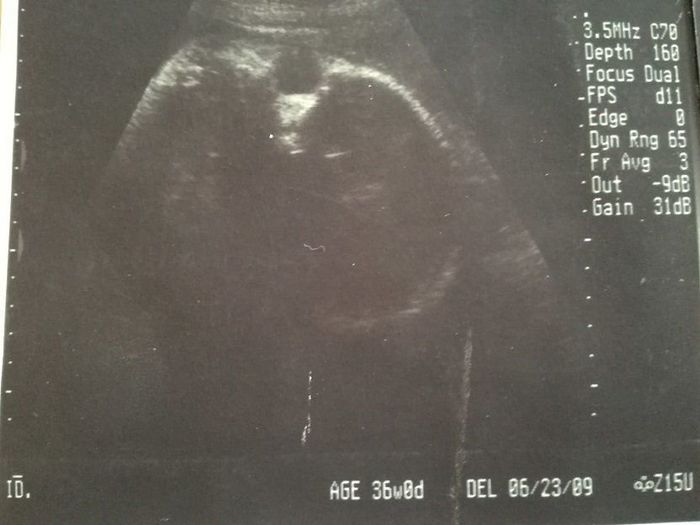

妊娠36週目エコー写真

赤ちゃんの心臓は元気に鼓動し、推定体重も2762gと順調。ただ、「おりもの検査」を受けた際に、子宮口が指2本ぐらい開いていると言われ、「1週間くらい安静に過ごしてください」と指導されました。「赤ちゃんの体重的には今生まれても大きな問題はないけれど、妊娠37週以降で産むのがベスト」とのこと。赤ちゃんに「あと少しママのおなかで過ごしていてね」とお願いしました。